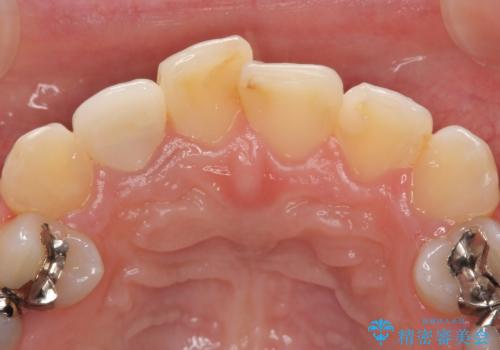

- 右上2番目の歯の被せ物と歯茎の間の継ぎ目が気になるといらっしゃった方の症例です。

再根管治療は希望されなかったため、クラウン除去後、オールセラミッククラウン(スペシャル)による補綴を行いました。